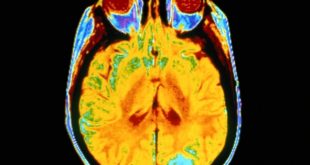

نوروسافاری | دانشمندان محل دقیق شبکه ای متشکل از سه بخش مغز را مشخص کردند که به نظر می رسد نقشی کلیدی در هوشیاری انسان داشته باشد. شما در حال خواندن این متن هستید، شما نسبت به کلمات، صفحه ی نمایش، دستگاه (الکترونیکی)، اتاق و زمان آگاه هستید، اما این …